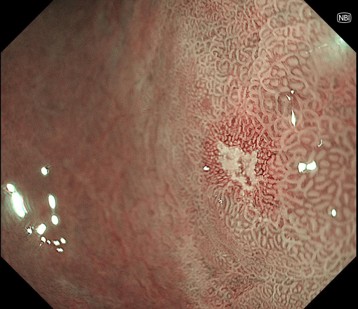

➂NBI(狭帯域光観察)併用非拡大観察

同部位に白色調変化あり

④NBI併用拡大観察

病変内は異型血管を認めず、窩間部の開大所見あり

生検病理: Group 5 (印環細胞癌)

専門病院へ紹介し、ESDで一括切除

病理診断 0-IIb, Adenocarcinoma, 4mm, pT1a(M), ly0 ,v0 ,HM0 ,VM0

(早期胃癌 粘膜内癌 脈管・リンパ管侵襲なく治癒切除)